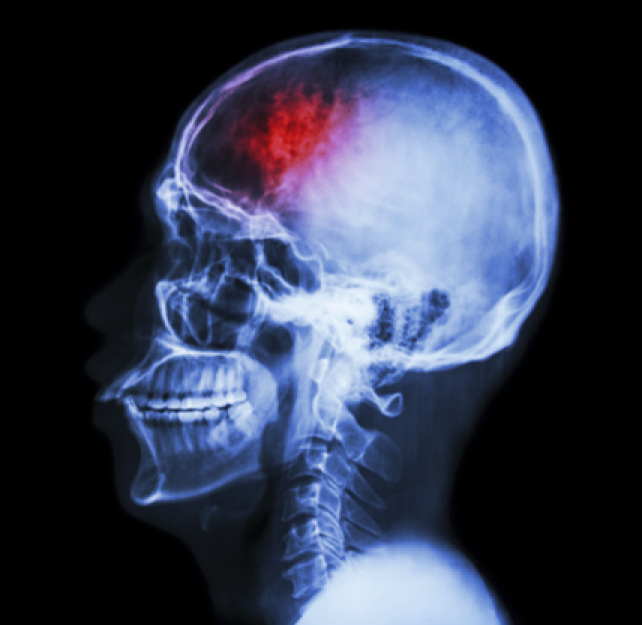

Brain Injury Symptoms